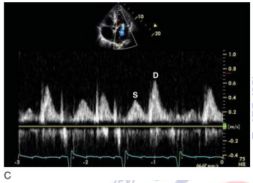

159.參考圖 A, B, C, 請問下列敘述何者錯誤?

(A) 此疾病早期 (early stage),還保有左心室收縮功能。 (B) 此疾病,左心室舒張末期壓力上升,影響左心房收縮血液至左心室,因此二尖瓣血 流 (mitral flow) 之 A 波通常變小。 (C) 此疾病,左心房壓力上升,影響肺靜脈血流 (pulmonary vein flow),造成肺靜脈血流 之流速在收縮期時 (S) 降低。 (D) 由於全面舒張期異常,因此,tissue Doppler 在二尖瓣環狀 (mitral annulus) 之 E’流 速通常小於 7 cm/sec。 (E) 此疾病主要是因為心包膜異常變厚,或是發炎,或是鈣化,而導致舒張期填充 (diastolic filling) 異常。